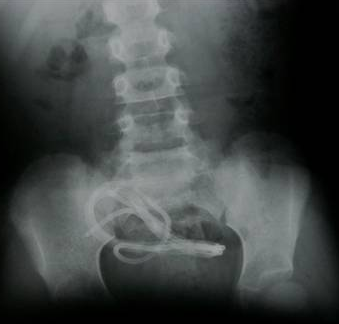

Galerinin tamamı için tıklayınızMideye kaçan sineği öldürmek için ağza sheltox sıkmak suretiyle ölüm (İstanbul/Sultanbeyli)

Mideye kaçan sineği öldürmek için ağza sheltox sıkmak suretiyle ölüm (İstanbul/Sultanbeyli)